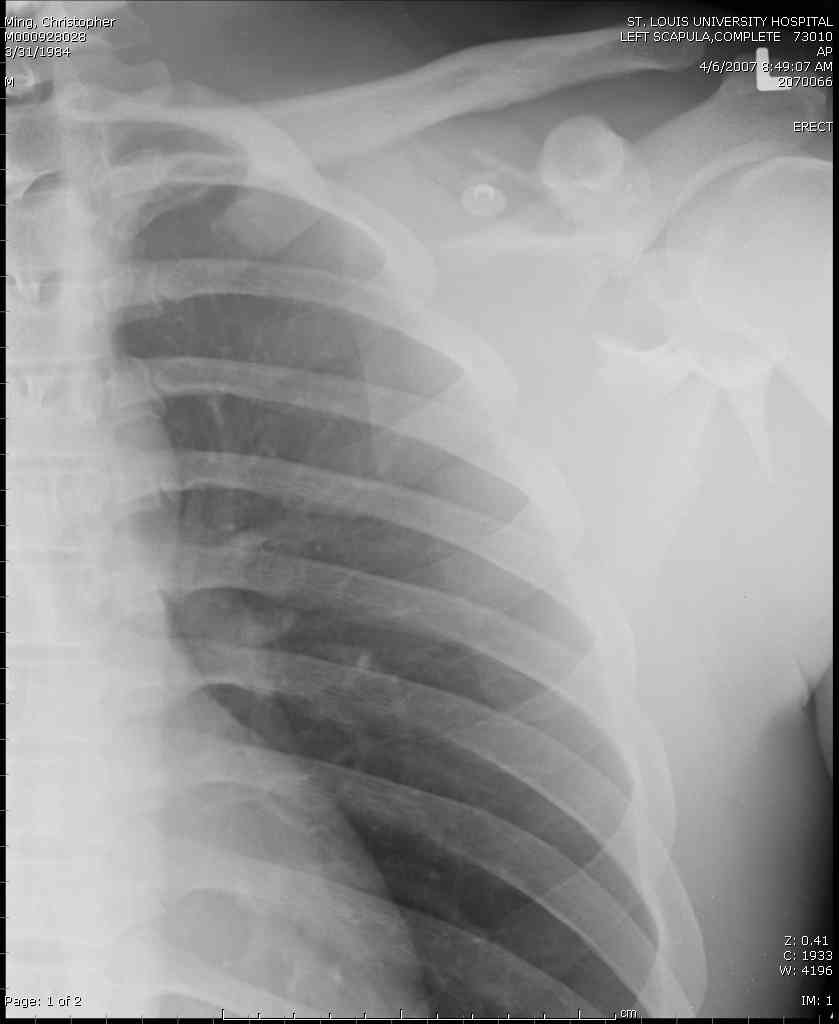

дравствуйте, коллеги. Мужчина 24 лет. Сегодня был прооперирован по Сушко-Илизарову (давно порывался, наконец-то руки дошли :)) На снимке перелом угла лопатки. Довольно крупный размер осколка. Следует ли оперировать такой перелом?Если есть резон оперативного лечения, то каким образом? (рекон. пластина, закрыто пришпилить спицами, винтами). ЭОПа в наличии нет. В области лопатки массивный отек мягких тканей. С уважением, Заднепровский Никита Николаевич

Для решения насчет оперативного вмещательства на лопатке сперва надо определиться с обьязательными ренгенологическими исследованиями, не менее трех стандартных проекций: прямая, аксиллярная и в позиции виде “Y”.

Прямую снимают под углом в 35 градусов от центра и вид “Y” в 90 градусов к нему. Несмотря на неудобства, больному необходимо сделать

аксиллярный снимок.

К-томографические и Трехмерные(3D)снимки крайне важны для определения внутрисуставных переломов и классификации.

Кроме анатомической классификации, переломы лопатки делятся на стабильные и нестабильные, внутри- и внесуставные и с вовлечением суставной поверхности.

Нестабильные внесуставные переломы лопатки типично сочетаются с переломами ключицы и ребер.

Посмотрел пациента под рентгеноскопом, определяется изолированный перелом верхнего медиального угла лопатки. Вопрос об операции отпал. Больной машет крылом как пропеллером, пришлось ограничить активность дисциплинирующей "косынкой" ... :))) Отек мягких тканей в области